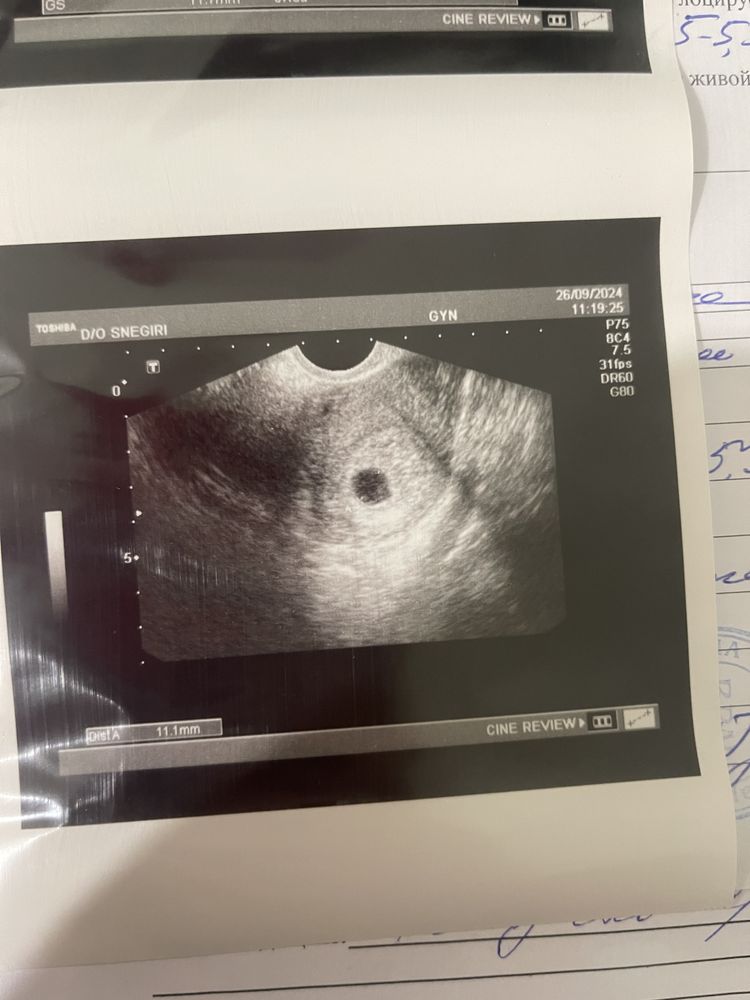

неделю назад когда пя был 11.7 врач сказала что все в матке есть и даже пульсацию поймала 70-80ударов, но сказала прийти через неделю тогда точно можно сердце услышаьь

С младшим пришла на УЗИ в 6,5 недель было пя 11 мм. Даже желтосного мешочка не было. Поставили под ? Анэмбрионию. Через неделю в 7,5 недель уже ктр был и сердечко билось. Перепроверьте, на чистку всегда успеете